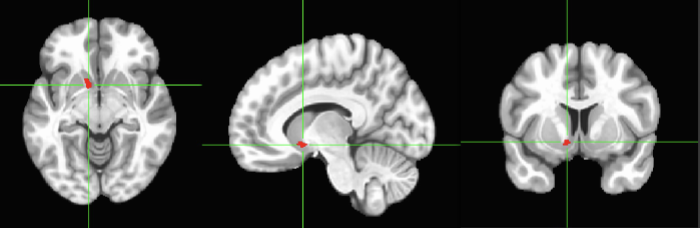

NUCLEUS ACCUMBENS– This is the left hemisphere, we have

a right NA as well. Both, left and right, are part of the

dopamine Reward pathway. Neurons in the VTA project DA to

the NA. This is what we call Reward pathway or Mesolimbic.

This pathway is a pathway studied in addictions.